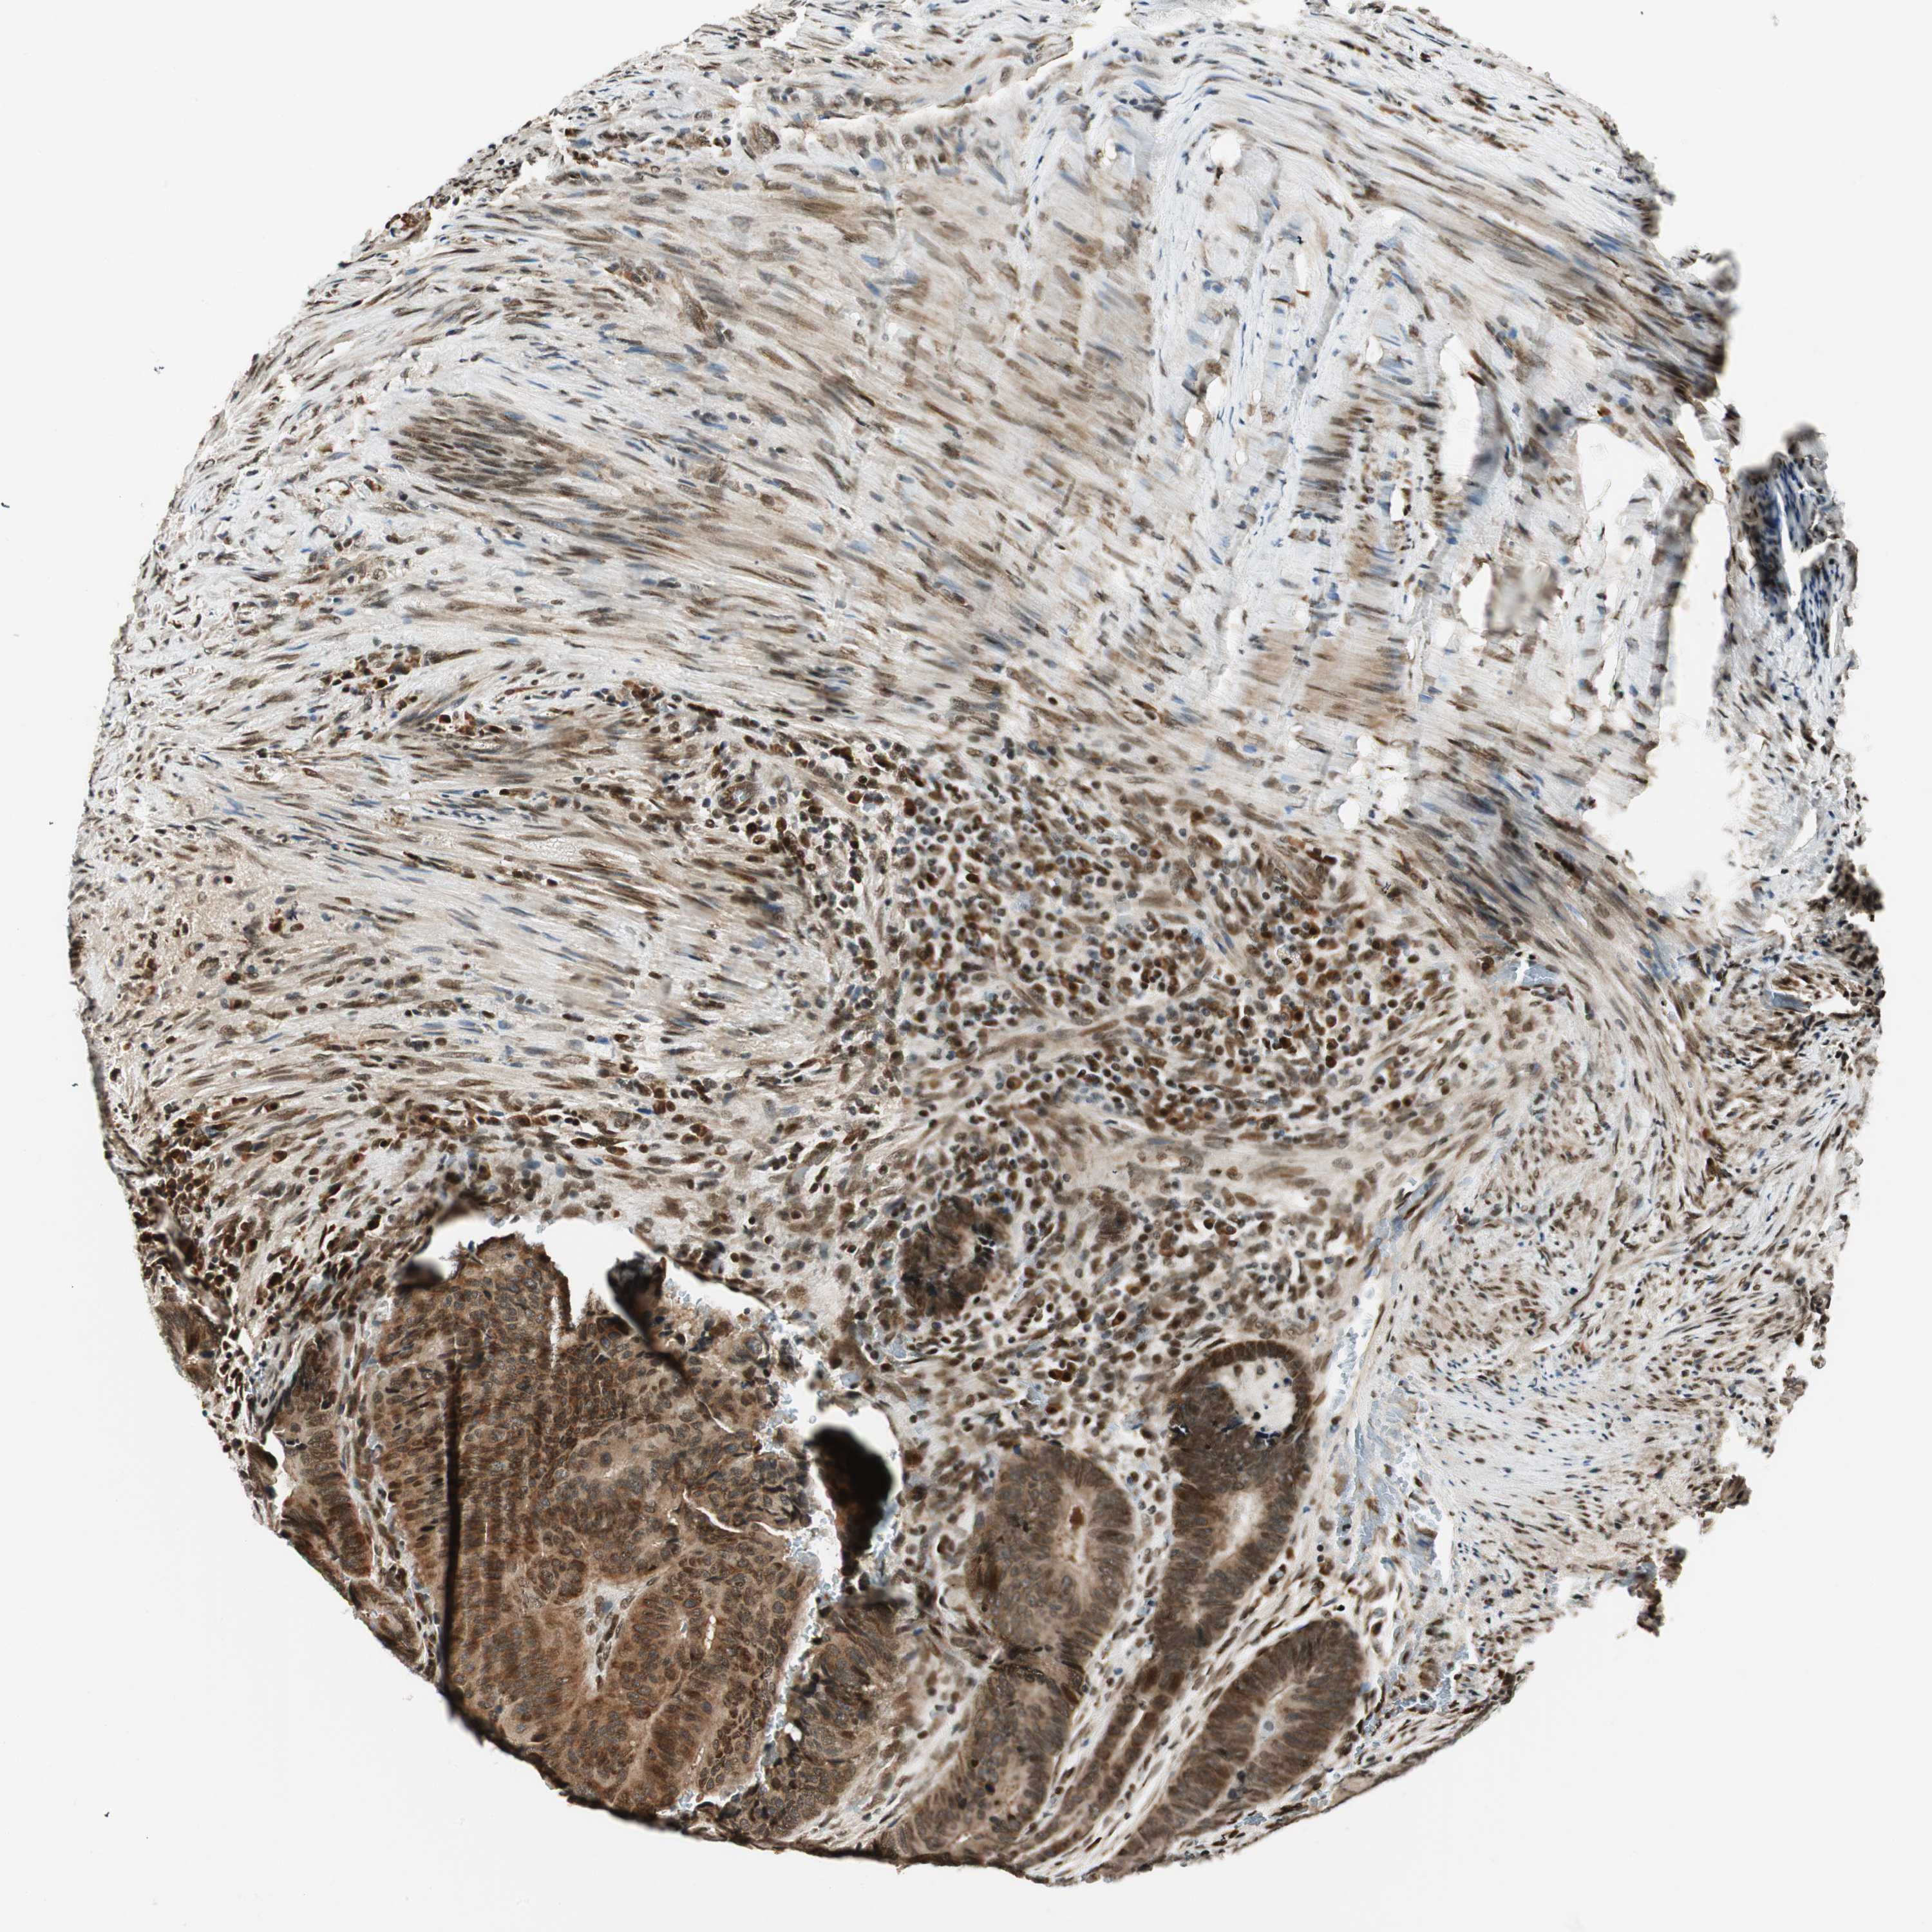

CANCER COLORECTAL CANCER Show tissue menu

Colorectal cancer

Human cancer

Colon adenocarcinoma